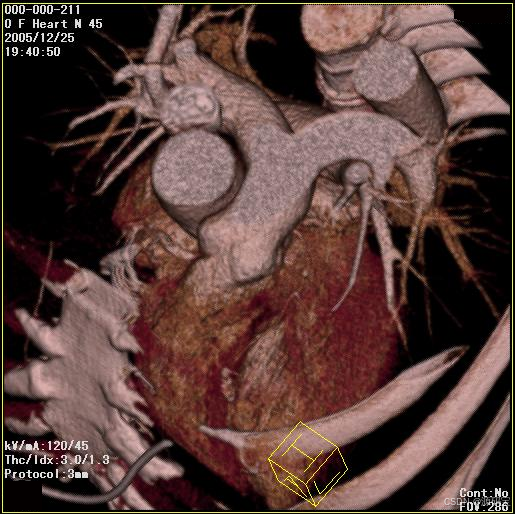

3、浏览图像

搜索到病人的影像信息后,可以在PACS系统中浏览和查看这些影像。系统会自动将病人的影像分成多个部位,可以根据需要选择浏览。